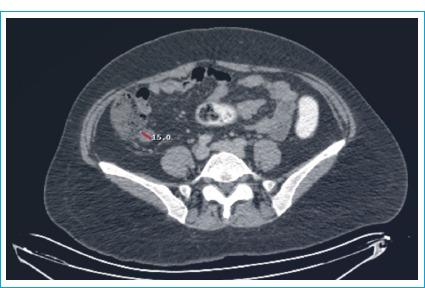

嗜铬细胞瘤是一种起源于肾上腺的罕见肿瘤,以分泌儿茶酚胺为特征。由于高血压危象与儿茶酚胺释放相关,嗜铬细胞瘤患者的手术治疗是有风险的。在这个病例报告,腹腔镜阑尾切除术急性阑尾炎患者谁有嗜铬细胞瘤将提出。女性,49岁,腹痛。体格检查显示右下腹有防守和反弹。患者在调查中有白细胞增多,腹部计算机断层扫描显示急性阑尾炎和5厘米右肾上腺肿块的迹象。六个月前内分泌科的腹部磁共振成像显示右肾上腺有一个39x32毫米的肿块,尿儿茶酚胺水平升高。据了解,该病人在此期间没有参加后续预约。患者接受内分泌科会诊,并进行了紧急腹腔镜阑尾切除术。患者于术后第2天出院,未出现任何并发症。患者转至内分泌科,开始进行嗜铬细胞瘤手术的术前准备。在紧急情况下,诊断为嗜铬细胞瘤的患者可以在适当的术前准备下进行紧急手术。

Pheochromocytoma is a rare tumor originating from the adrenal gland, characterized by the secretion of catecholamines. Due to the risk of hypertensive crises associated with catecholamine release, surgical procedures in pheochromocytoma patients are risky. In this case report, laparoscopic appendectomy for acute appendicitis in a patient who has pheochromocytoma will be presented. A 49-year-old female patient presented with abdominal pain. Physical examination showed guarding and rebound in the right lower quadrant. The patient, who had leukocytosis in the investigations, showed signs of acute appendicitis and a 5 cm right adrenal mass on the abdominal computed tomography. A previous abdominal magnetic resonance imaging by the endocrinology department six months ago revealed a 39x32 mm mass in the right adrenal gland and elevated urinary catecholamine levels. It was learned that the patient had not attended follow-up appointments during this period. The patient was consulted by endocrinology and an emergency laparoscopic appendectomy was performed. The patient, discharged on the 2nd day after surgery, did not experience any complications. The patient was referred to endocrinology, and preoperative preparations for pheochromocytoma surgery were initiated. In cases of emergency in patients diagnosed with pheochromocytoma emergency surgery can be performed with appropriate preoperative preparation.